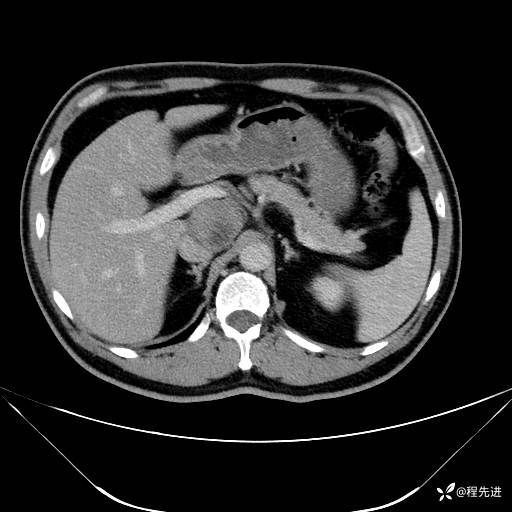

【腹盆】特别精彩病例|发现腹膜后肿物1月余

主诉:发现腹膜后肿物1月余

现病史:患者1月余前查体,行超声检查提示:后腹膜囊实性肿块;慢性胆囊炎伴胆囊内结石;无腹痛腹胀,不伴腹泻发热等;偶感腰背部酸痛。

CT平扫+增强: